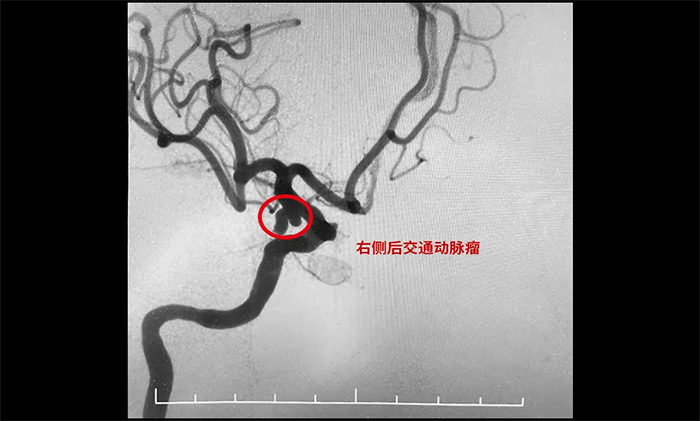

《長江日報》2023年10月18日報道,55歲的張女士參加家庭聚會唱《青藏高原》飆高音時,突然頭疼劇烈、惡心嘔吐,家人緊急將其送醫(yī)。醫(yī)院給她做了全腦血管造影,最后發(fā)現(xiàn)是動脈瘤破裂。

▲ 栓塞前

▲ 栓塞后